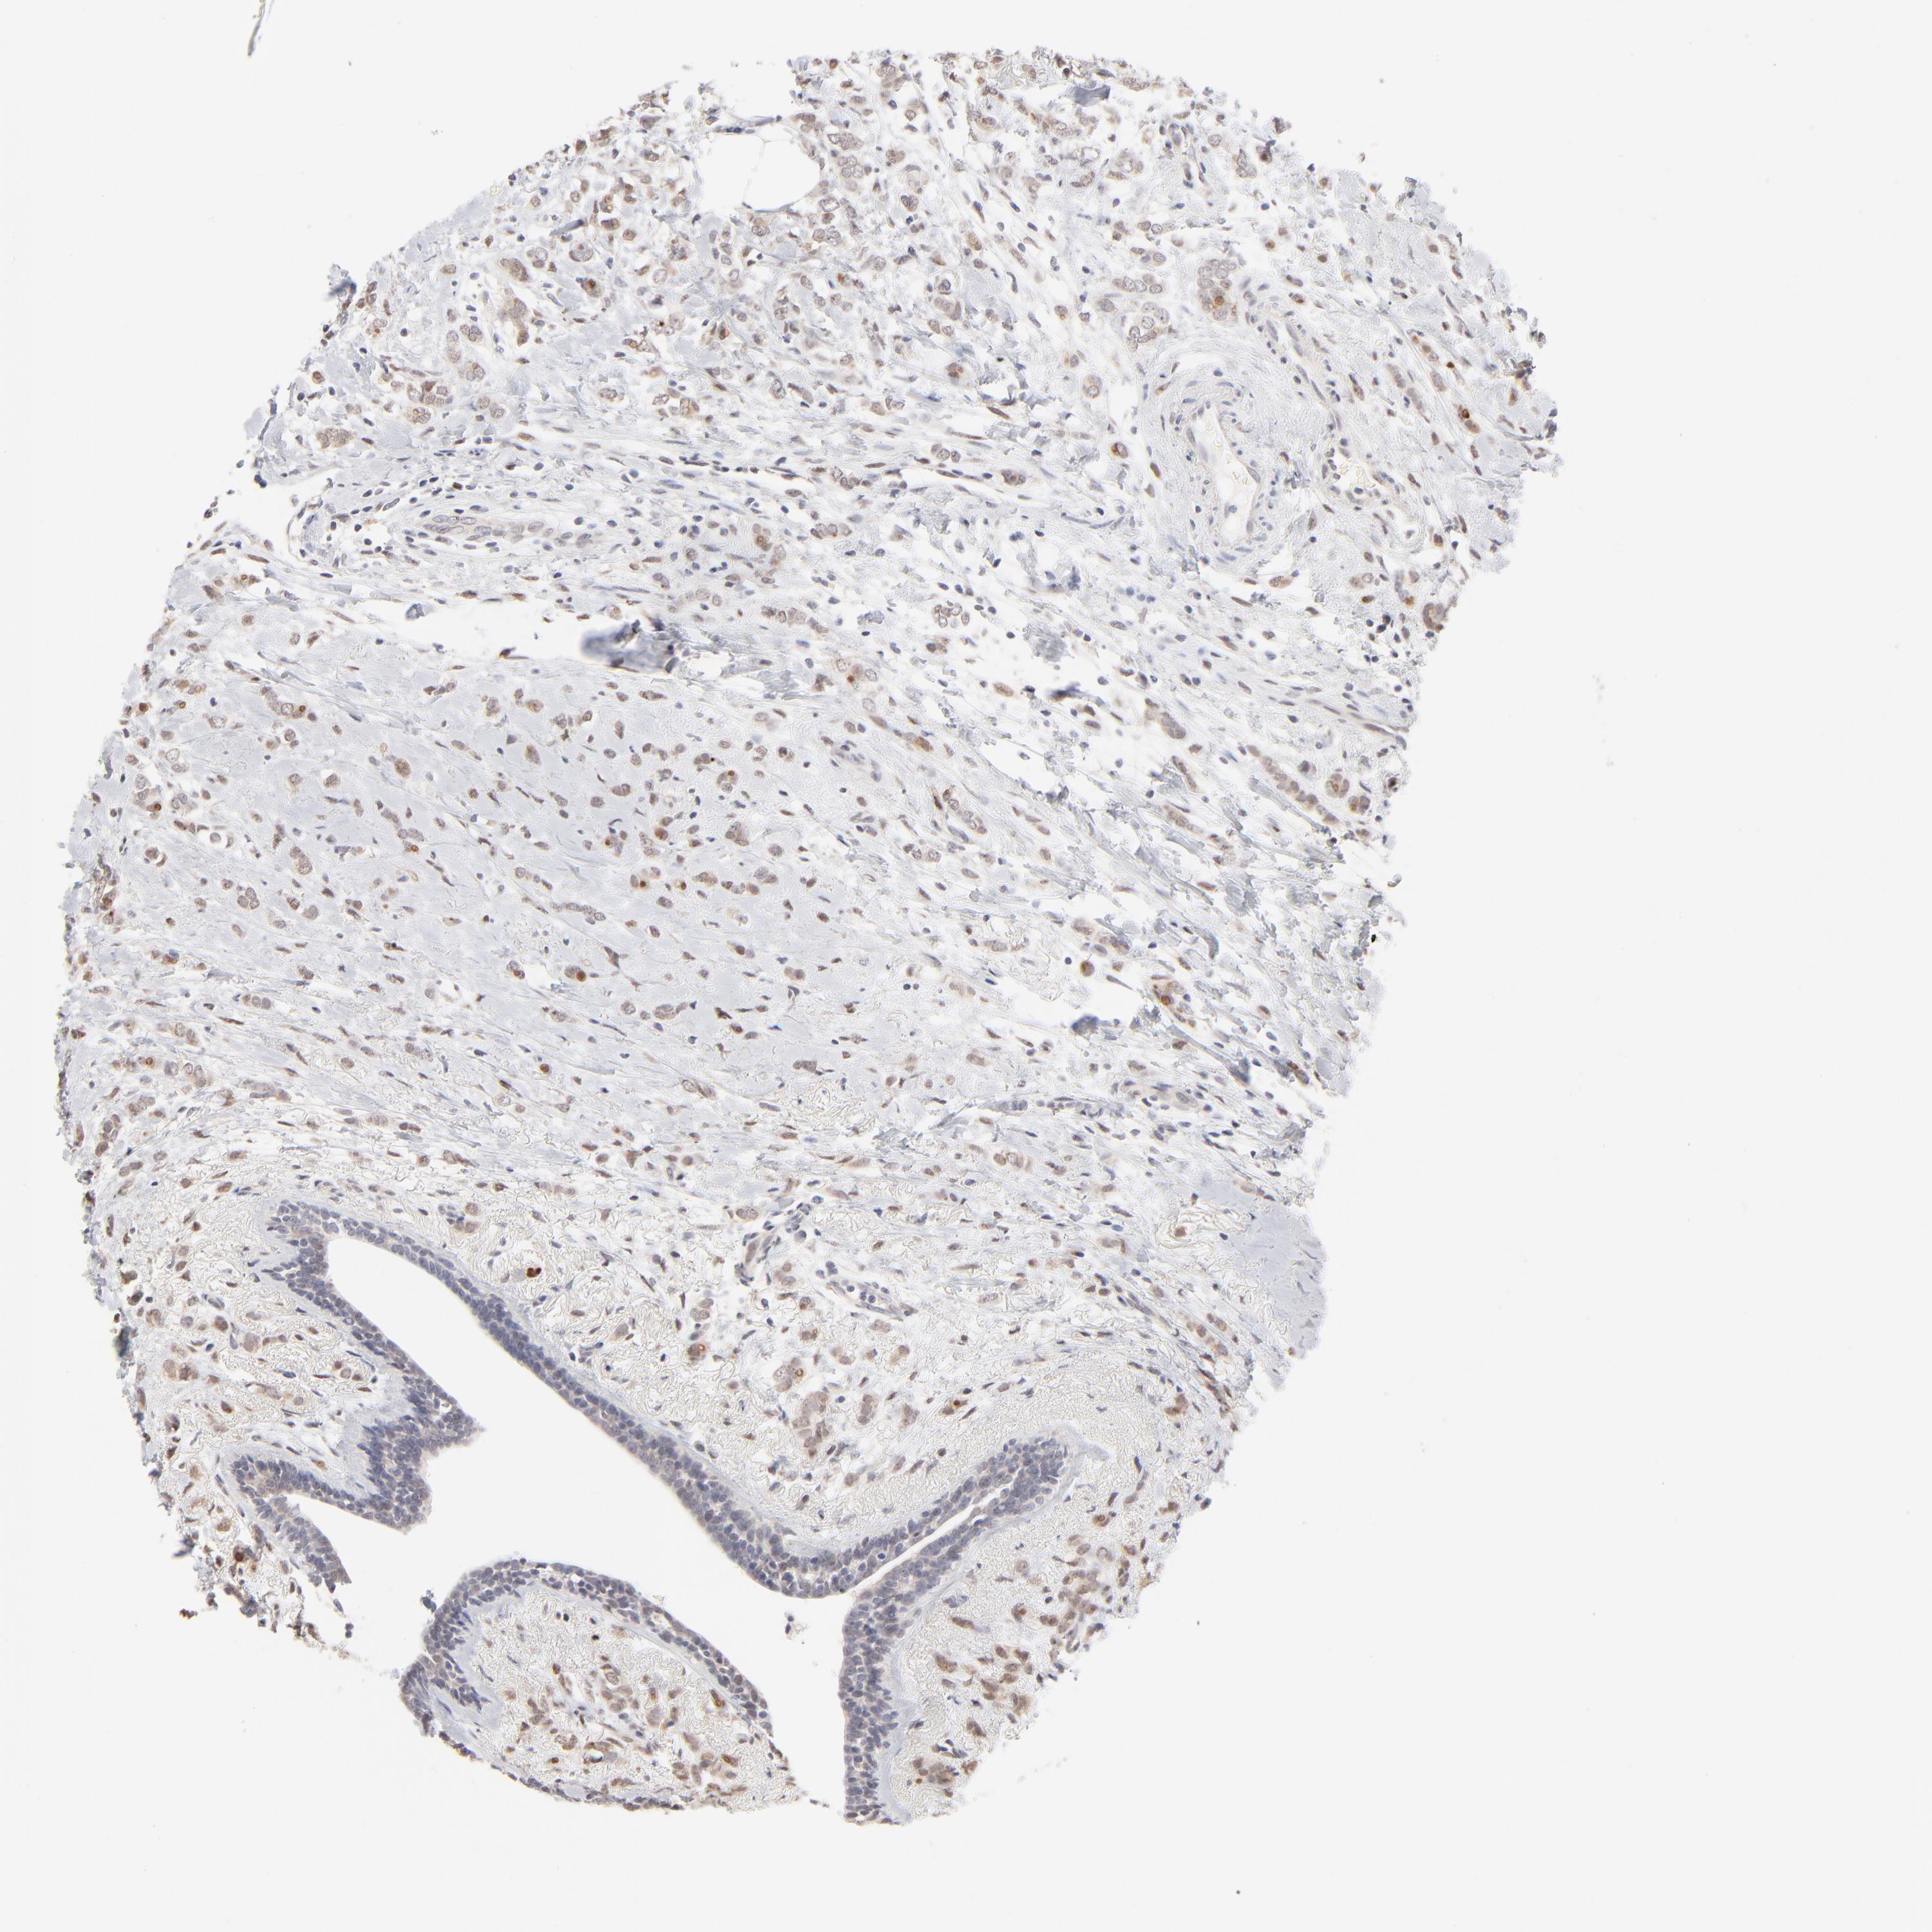

CANCER BREAST CANCER Show tissue menu

BRCA TCGA BRCA VALIDATION PROTEIN EXPRESSION